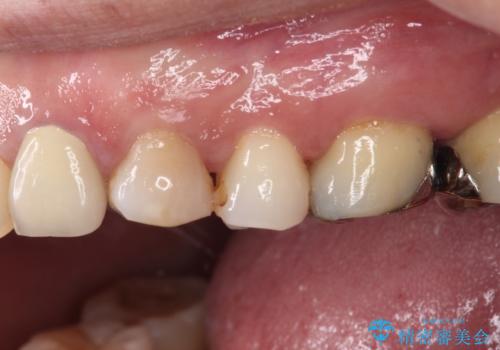

- 食事の度に痛みを感じるとのことで来院された患者様です。

診査の結果、既に歯の神経は失活していたおり、叩いたり触ったりしたときの痛みも確認されました。

まずは根管治療を行い、その後にオールセラミッククラウンにて補綴することとしました。